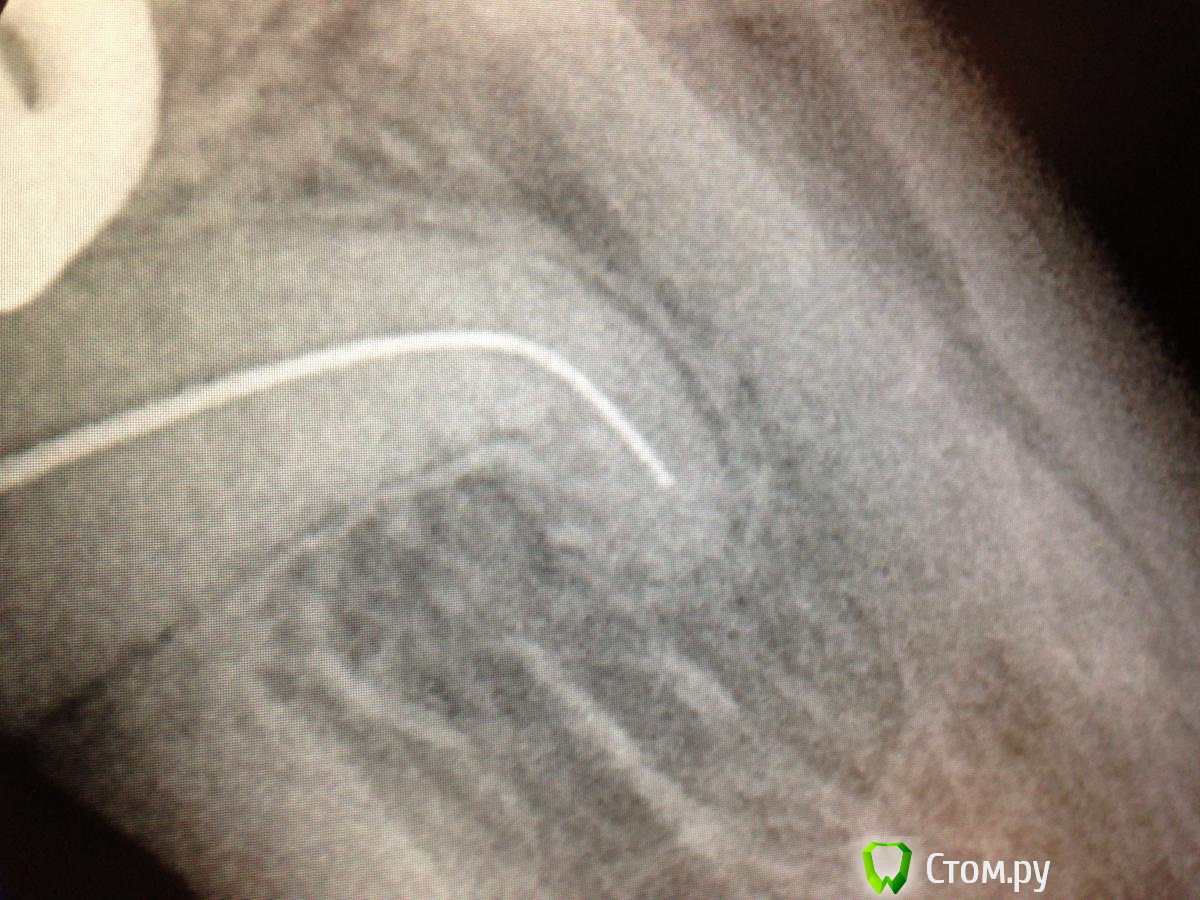

SSTi Опубликовано 20 мая, 2014 Автор Поделиться Опубликовано 20 мая, 2014 пульпитный 35. с сюрпризом в виде кривульки. Доступ дистально. коффер, обработка ручными к-файлами, машинные протейперы( до ф2), профайлы. Много гипохлорита, уз.Все время было чувство, что сломаю файл за изгибом, или нарежу ступень... но пронесло)) боялся, что не дойду до апекса(апекслокатор не начинал пока даже попискивать), потом дошел, отступил 0,5, сделал упор и вот тебе результат- вышел на 0,5.... 8 Ссылка на комментарий

SSTi Опубликовано 20 мая, 2014 Автор Поделиться Опубликовано 20 мая, 2014 (изменено) Спасибо)Я никогда не забуду хруст протейперов в этой пятерке и мысли о том, как доставать если вдруг ...))) что-то везет в последнее время на кривули такие. Кстати рд здесь-25.5 мм. Напрягает, когда эндонаконечник вплотную к зубу и ты не видишь файла..... Изменено 20 мая, 2014 пользователем SSTi Ссылка на комментарий